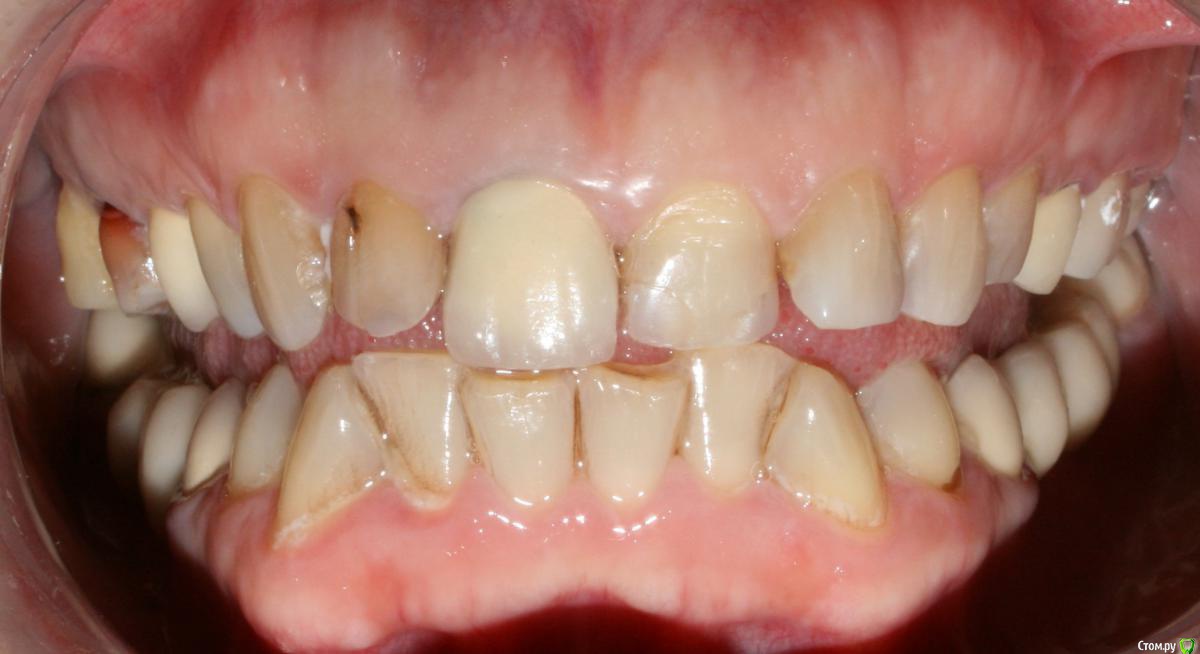

kramer Опубликовано 17 января, 2018 Поделиться Опубликовано 17 января, 2018 (изменено) Коллеги, добрый вечер. Помогите начинающему ортопеду. Заранее прошу простить за качество фото. Пациентка обратилась с целью улучшения эстетики фронтальных зубов. Около года назад один врач из нашей клиники делал м/к на боковые зубы (пациентку устраивают), при этом, по всей видимости, было снижение прикуса из-за стирания, но его высоту не восстанавливали. Теперь настало время передних зубов, и работать, получается, придется с имеющейся высотой. План лечения: 14, 24 - м/к, 13-23 имакс коронки/виниры. Меня смущают фасетки стираемости на клыках в/ч. Вопрос: каким образом лучше их реставрировать во избежание сколов реставраций? Делать полные коронки? Спасибо, надеюсь на ваш совет. Изменено 17 января, 2018 пользователем kramer Ссылка на комментарий

StomV Опубликовано 22 января, 2018 Поделиться Опубликовано 22 января, 2018 Я не пойму,почему все в один голос твердят,что здесь нужно поднимать прикус?Какие показания? С чего вы это решили?Нужно исходить из возраста пациента. Да здесь видны фасетки стираемости,но не стоит забывать,что есть еще компенсация стираемости в виде роста альвеолярного отростка с зубами (гипертрофия) и далеко не всегда стираемость приводит к снижению МАВ. Здесь как раз намного важнее определиться с ЦС и ВНЧС,как минимум провести тесты,сделать КТ сустава.Если все в норме,то нет нужны поднимать высоту. Я думаю в данной клинической ситуации возможно отмоделировать достточно неплохо фронт,хотелось бы увидеть ваш вариант воска. 1 Ссылка на комментарий

kramer Опубликовано 23 января, 2018 Автор Поделиться Опубликовано 23 января, 2018 LVI измерьте и подсчитайте надо ли поднимать высоту или нет. Попробовал, даже судя по фото №2, где зубы сомкнуты не до конца, не хватает высоты Ссылка на комментарий